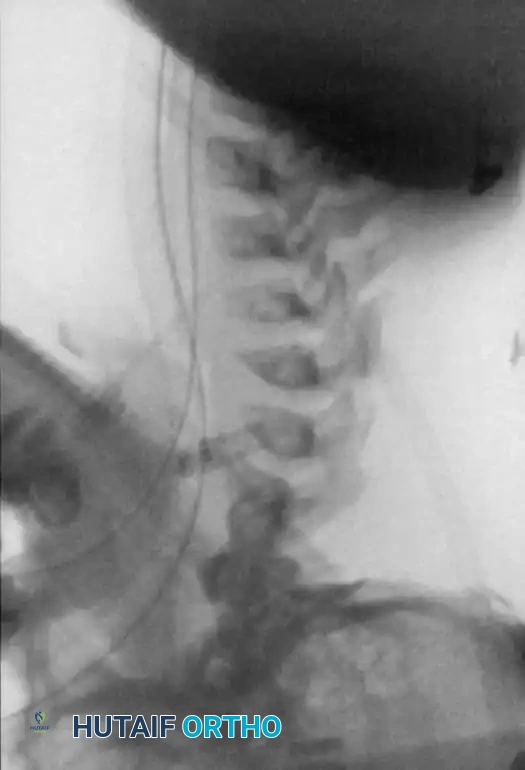

Fig. 38-218 A, Progressive cervical kyphosis in a 13-year-old girl treated for a low-grade astrocytoma with laminectomy and radiotherapy. Note the severe anterior vertebral wedging.

Fig. 38-218 B, Radiograph demonstrating partial reduction of the kyphotic deformity utilizing preoperative halo traction.

Fig. 38-218 C, Postoperative radiograph demonstrating restoration of sagittal alignment following combined anterior and posterior fusion.